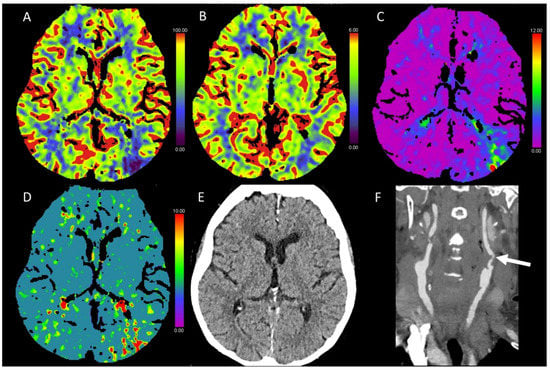

3.5. Hypotensive Cerebral Infarction (HCI) with Watershed Infarcts/Border Zones

3.7. Migraine

3.8. Luxury Perfusion